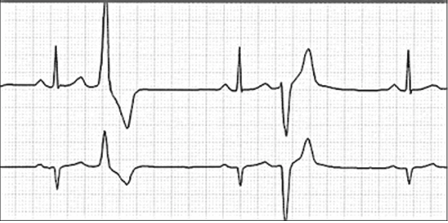

First Degree Heart Block

2nd Degree Block Type 1

2nd Degree Block Type 2